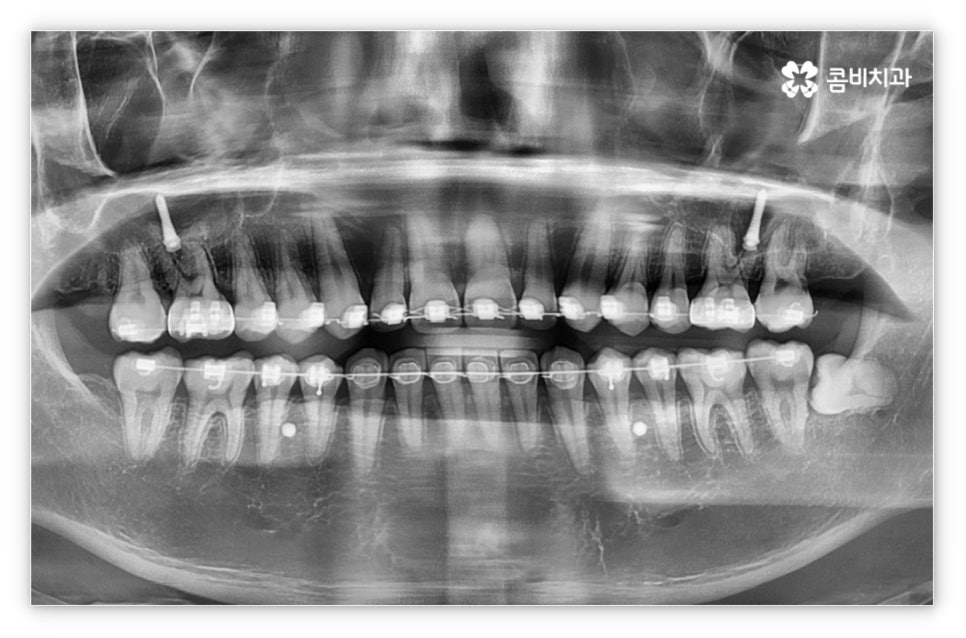

살펴본 바와 같이 앞니설측교정 의 장점에도 불구하고 아랫니 부분은 장치가 혀에 닿게 되기 때문에 환자분들께서 불편함을 느낄 수 있고 혹시라도 혀가 브라켓에 잘못 쓸리거나 눌렸을 때 통증이 발생할 수도 있으며 발음이 불분명해지는 문제가 생길 수 있는데요. 이러한 이유로 앞니설측교정 에 대해서 고민이 되시는 분들은 윗니 부분은 설측으로, 아랫니 부분은 일반 교정처럼 순측으로 진행하는 콤비 교정에 대해서 알아보시면 좋을 거예요. 위의 사진에서 살펴보실 수 있는 경우가 바로 이렇게 콤비 교정으로 진행한 환자분의 케이스인데 아랫니의 경우 보통 입술에 가려 별로 드러나지 않는 데다가 치아 색상인 세라믹 재질로 된 브라켓을 이용하기 때문에 설측 교정과 비교해도 심미성이 크게 떨어지지 않는다는 것을 알 수 있어요. 콤비 교정의 경우 설측 교정보다 비용적인 부담도 줄일 수 있으니 각 장치에 대한 장단점을 의료진분들과 충분히 상담하셔서 자신에게 맞는 장치를 선택하시면 좋을 거예요.